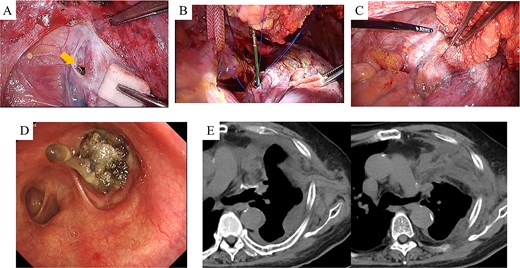

After harvesting the latissimus dorsi flap through a posterolateral incision, a thoracotomy was performed. Intrathoracic adhesions were dissected to expose the bronchial stump fistula, which measured ~10 mm (Fig. 2A); no evidence of empyema was observed. Given the large, deep configuration of the fistula, which would complicate delivery and complete coverage of the flap, a bronchoscope was inserted and biopsy forceps were advanced through the fistula into the thoracic cavity. The latissimus dorsi flap was grasped with the forceps, guided into the thoracic cavity, and secured in place with sutures (Fig. 2B). Fibrin glue was applied around the repair site for reinforcement (Fig. 2C). After confirming the absence of any air leak, the procedure was completed (Supplementary video 1). The operation lasted 140 min, with an estimated blood loss of 20 ml. The postoperative course was uneventful. On postoperative day 7, CT and bronchoscopy confirmed that the latissimus dorsi muscle had retrogradely filled the bronchial lumen and that the fistula was completely closed (Fig. 2D and E). The patient was discharged 13 days postoperatively, and home oxygen therapy was discontinued. Follow-up CT scans at 3 months showed gradual retraction of the latissimus dorsi muscle from the bronchial lumen, yet no residual air space was observed (Fig. 3A). At 6 months, bronchoscopy revealed satisfactory granulation tissue formation at the upper lobe bronchial stump, indicating complete healing (Fig. 3B).

Intraoperative and early postoperative findings. (A–C) Panel A identifies the fistula at the upper lobe bronchial stump (arrow), adjacent to the pulmonary artery. Panel B shows a bronchoscope being used to guide the biopsy forceps from the fistula site into the thoracic cavity to grasp the latissimus dorsi muscle flap. Panel C shows the flap secured into the bronchial lumen in a retrograde fashion, with fibrin glue applied for reinforcement. (D) Bronchoscopic view on postoperative day 7 confirms visibility of the latissimus dorsi muscle flap within the bronchial lumen. (E) CT scans on postoperative day 7 demonstrate secure suturing of the latissimus dorsi muscle flap to the fistula site and resolution of the preoperative airspace.